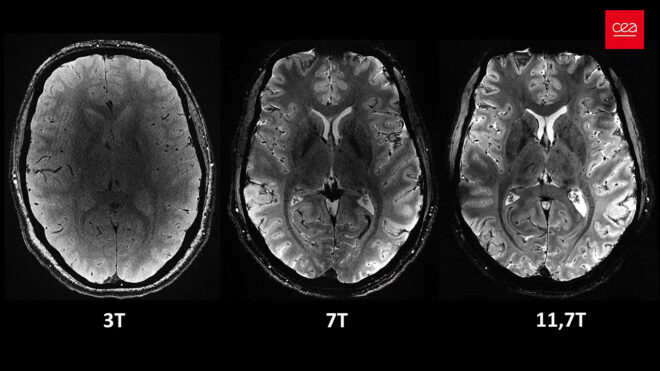

Fransa Alternatif Enerjiler ve Atom Enerjisi Komisyonu (CEA) tarafından geliştirilen Iseult MRI makinesi, aktarıldığı kadarıyla tam 11.7 Teslas (T) gücünde çekim gerçekleştirebiliyor. Söylendiği kadarıyla hastanelerde kullanılan normal MRI makineleri genelde 3 Teslas (T) gücün üstüne çıkmıyor, bu gerçekten çok ciddi güç farkı sayesinde normalden daha yüksek detay alınabiliyor. Yukarıdaki görüntüler de bahsi geçen makine ile kayıt altına alınan ilk insan beyni detaylarını karşımıza getiriyor. Bizim farkı anlamamız elbette çok zor ancak görsellerde doktorların normalde görmediği inanılmaz detayların olduğu, bu detayların beynin nasıl çalıştığını daha iyi anlamamıza ve nörodejeneratif hastalıkları (Alzheimer ve Parkinson gibi) daha iyi şekilde tedavi etmemize yardımcı olacağı söyleniyor. Normal MRI sistemleriyle böyle detaylı görüntülerin alınması için bir hastanın tam iki saat boyunca yatarak hareketsiz kalması gerekirken, “Iseult” ile sonuç sadece dört dakikada alınabiliyor. Gücüne bağlı olarak çok büyük olduğu aktarılan 132 tonluk makinenin, içindeki mıknatısları soğutmak için tam 7.500 litre sıvı helyum kullandığı aktarılıyor.